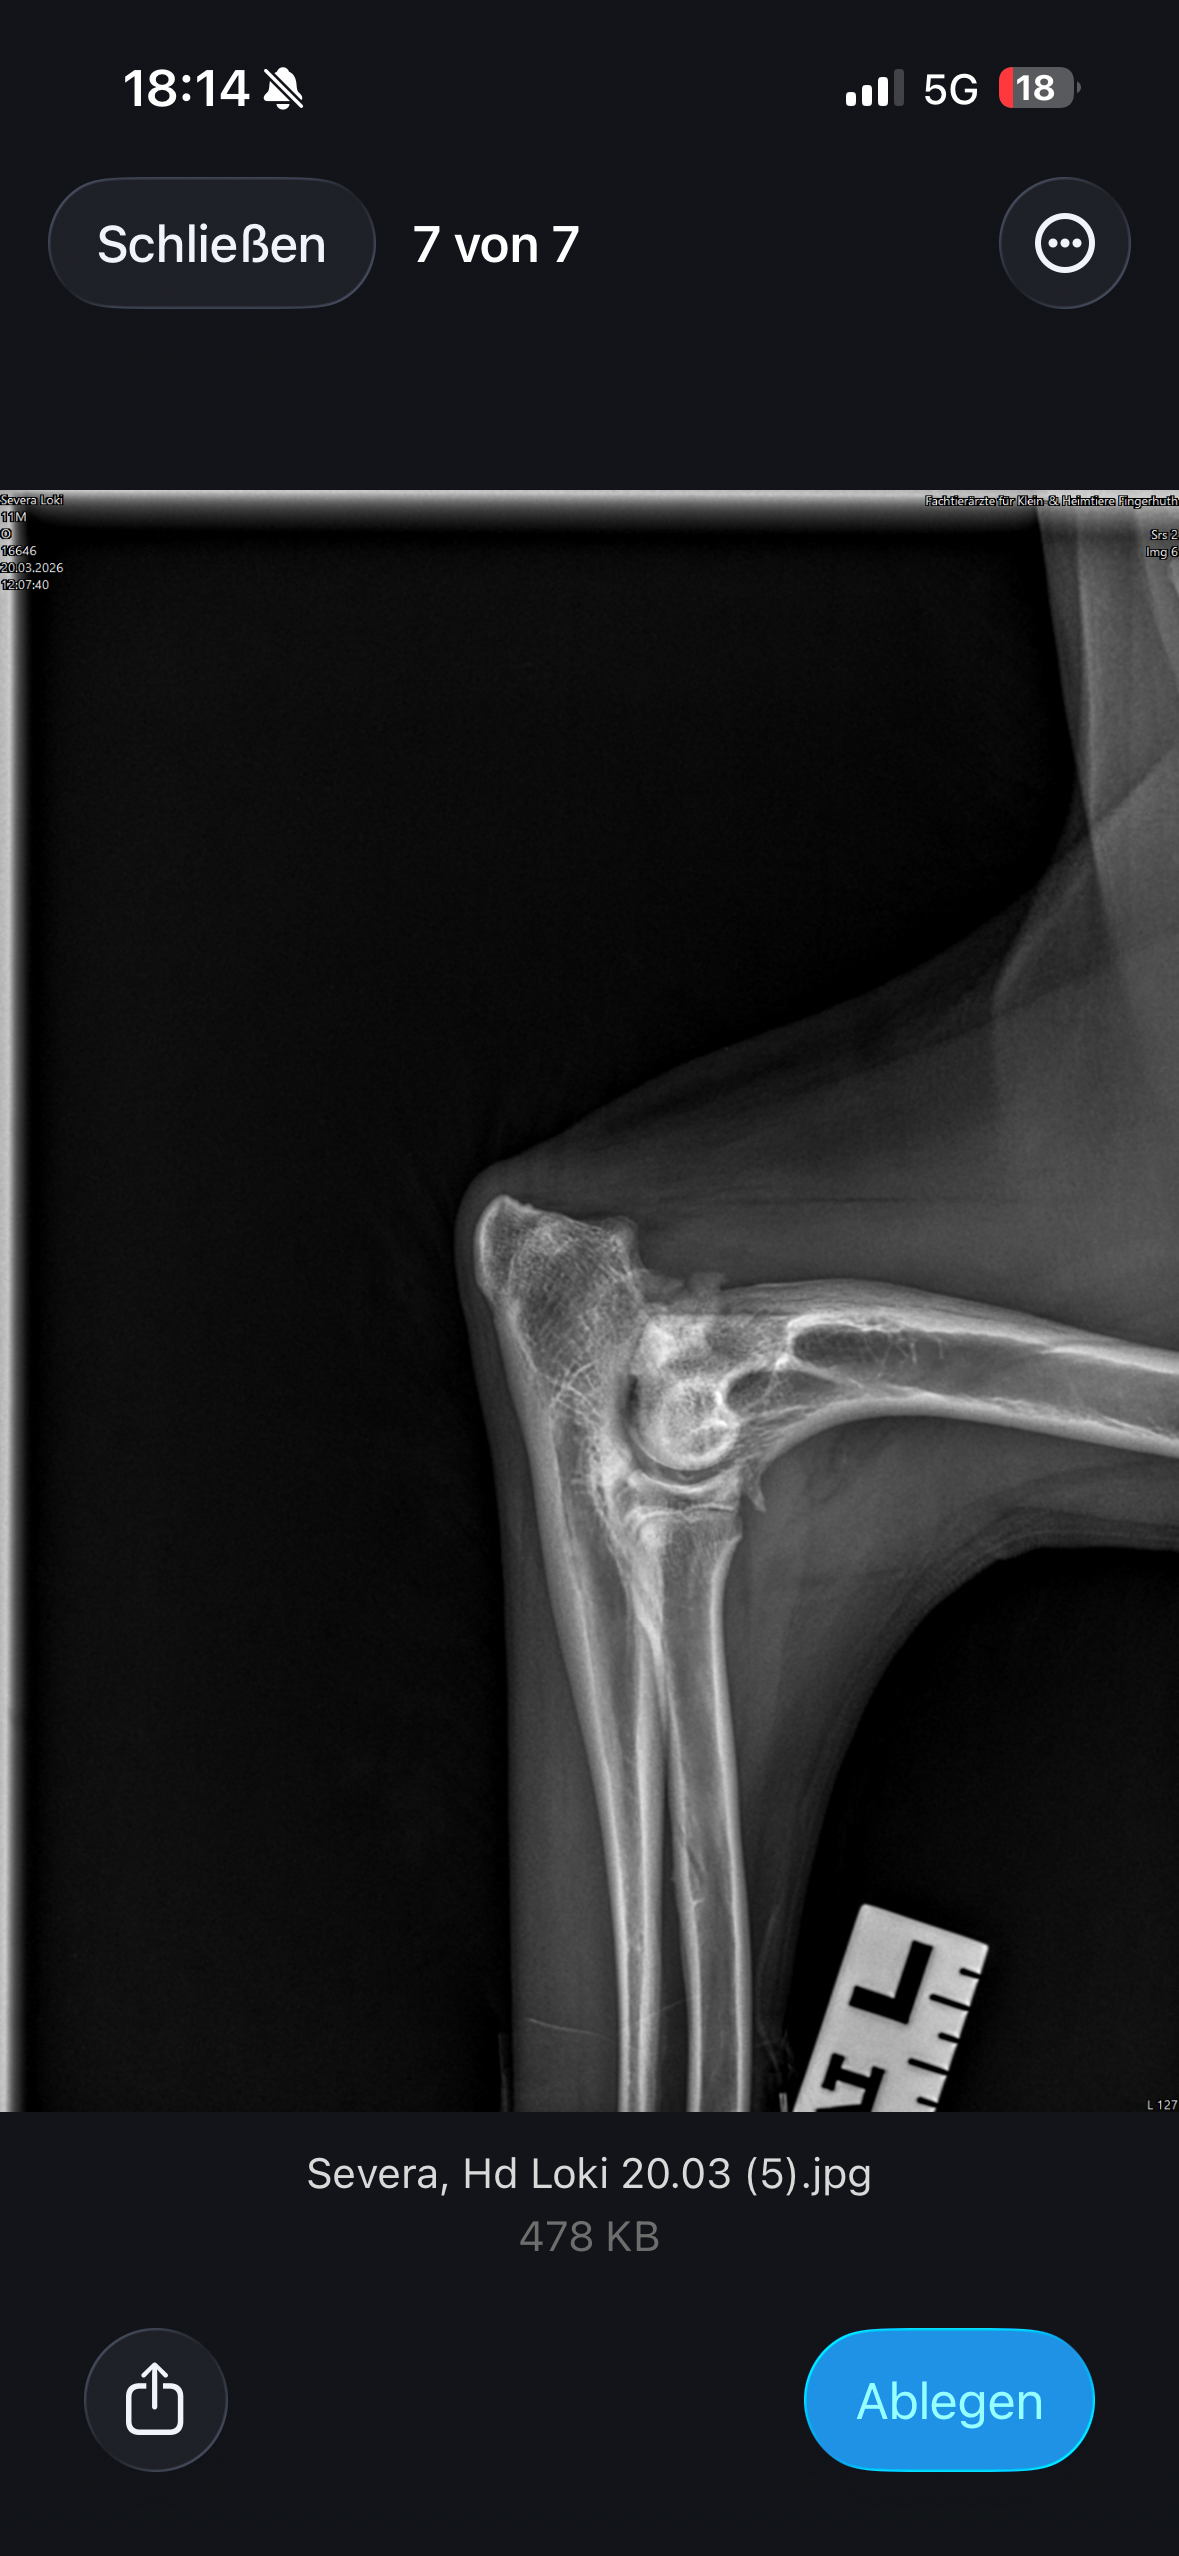

Loki leidet an Ellenbogendysplasie und Hüftdysplasie, jeweils auf beiden Seiten, was mehrere große und schwere Operationen erfordert, um ihm ein „so gut es geht“ schmerzfreies Leben zu ermöglichen. Die Gesamtkosten für die erforderlichen Behandlungen belaufen sich auf etwa 20.000 €, zu denen zusätzlich Behandlungskosten von mindestens 10.000 € für Physiotherapie, Medikamentengabe und weitere Maßnahmen kommen.

Röntgen, CT, Blutuntersuchung,mind. 3 große OP’s, Künstliche Hüftgelenke beidseits, Schmerzmittel, Physio, Wasserlaufband